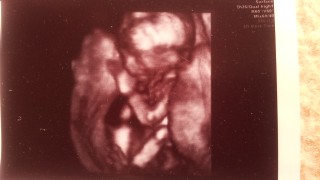

初めて3D写真もらえました!凄くハッキリ映っててビックリ★ 心音も力強く、順調との事です。 既に親バカですが、足がスラリと長い!!

5年間デキず、やっとお腹にきてくれた赤ちゃん♡指吸ってるところ♡